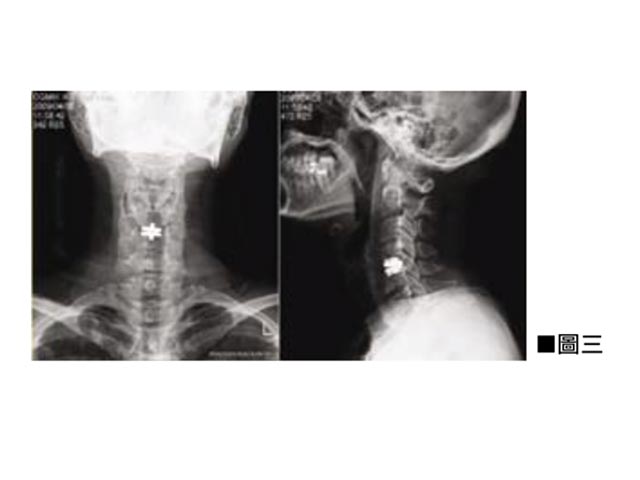

手術前醫生會和病人商討,根據病人的病情和需要來決定做手術的頸椎節數,和選擇固定式又或是非固定式的人工椎間盤。一般而言如果病人頸椎因為不穩定而導致頸痛或頭痛,又或者其脊髓中樞神經已經嚴重受壓而出現病變,非活動式的就是首選,可根治不穩定的痛症及免卻脊髓日後繼續受損的可能性。如果需要做多過一節的頸椎手術,例如牽涉三節頸椎,醫生可能建議其中一至兩截用活動式人工椎間盤,其餘用非活動式,這樣一來既可以維持頸椎的穩定性,亦可以得到相當程度的頸椎活動彈性。(見圖三)